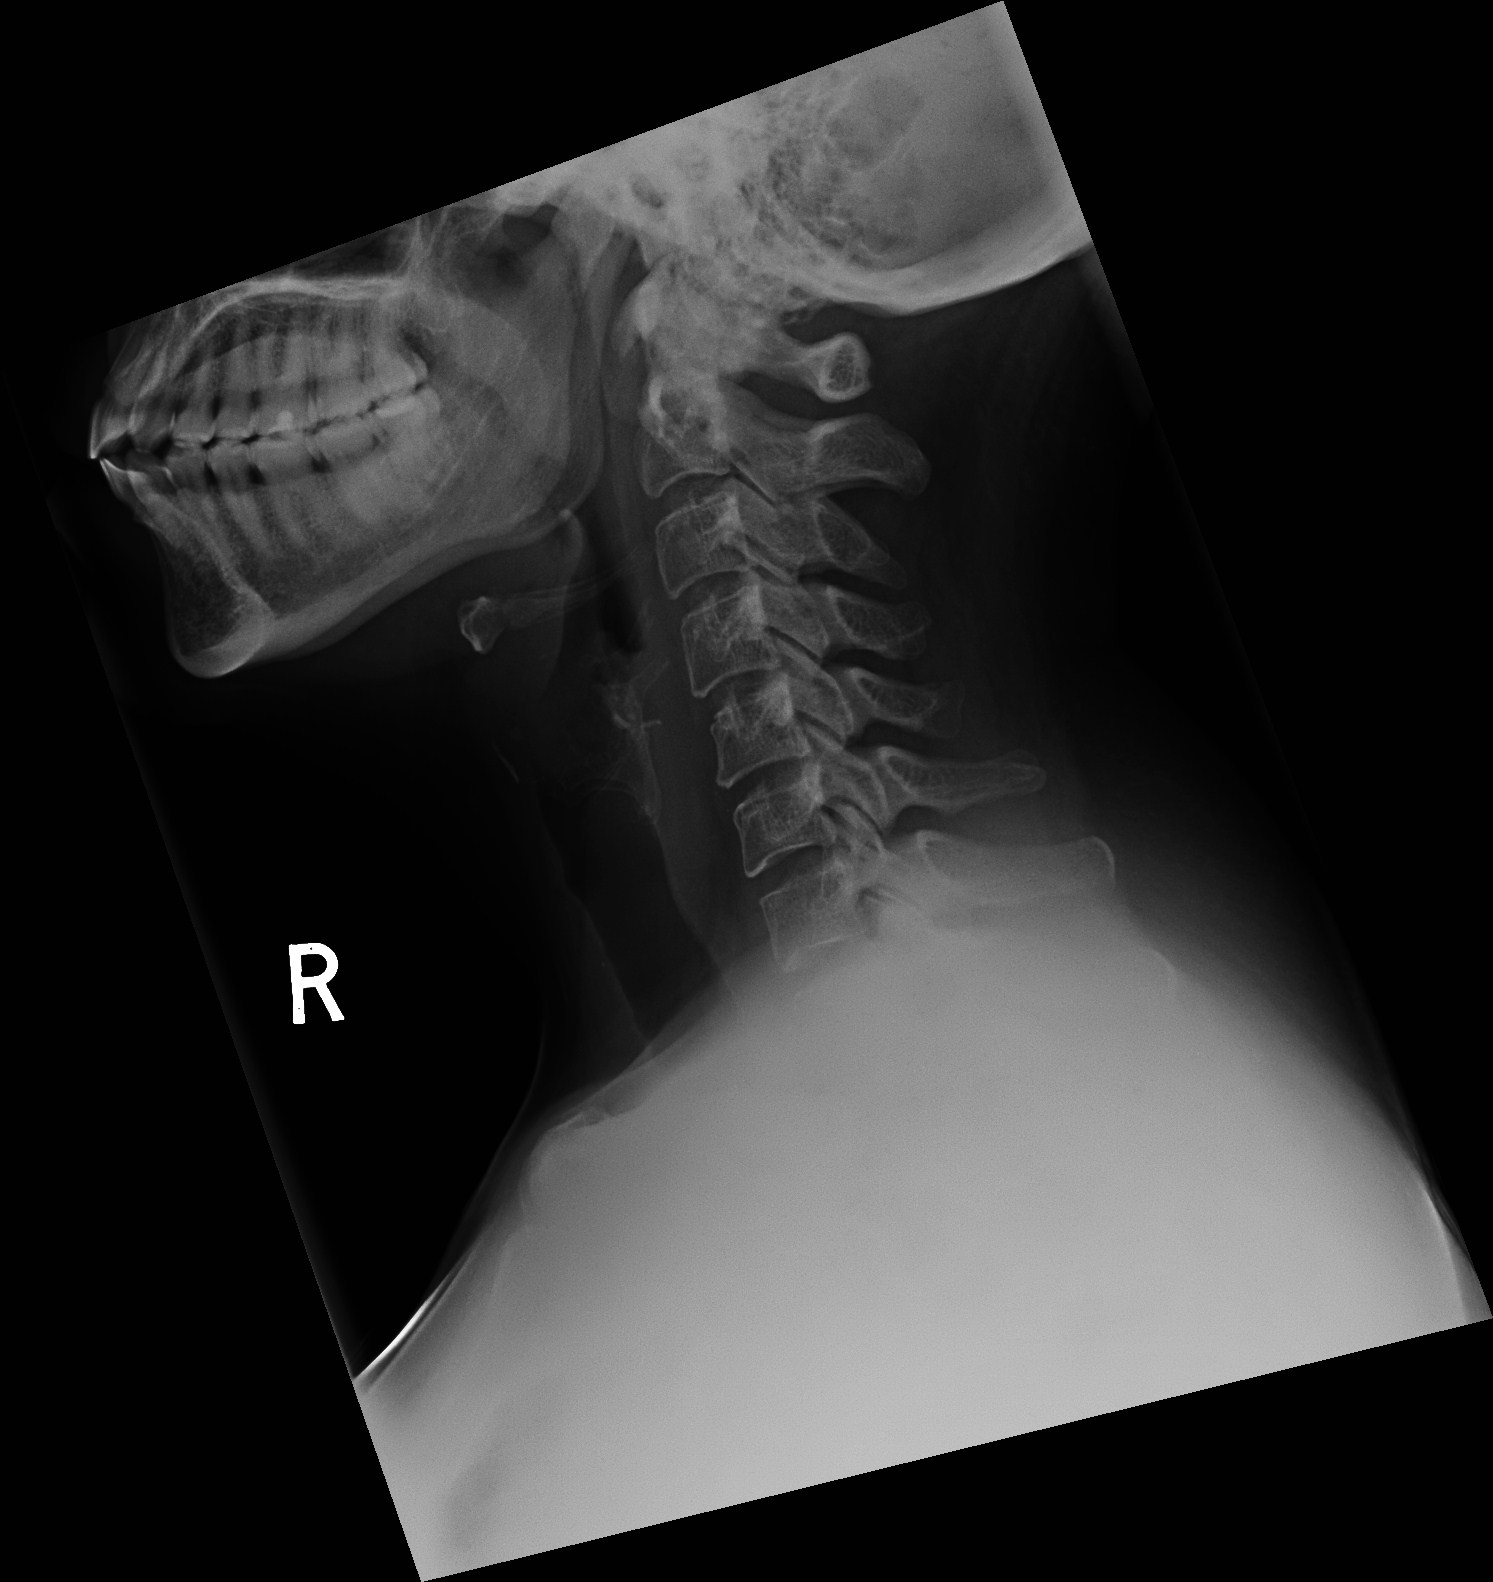

X-rays use invisible

electromagnetic energy beams to produce images

of internal tissues, bones, and organs on film

or digital media. Standard X-rays are performed

for many reasons, including diagnosing tumours or

bone injuries.

When the body undergoes X-rays, different parts

of the body allow varying amounts of the X-ray

beams to pass through. The soft tissues in the

body (such as blood, skin, fat, and muscle)

allow most of the X-ray to pass through and

appear dark gray on the film or digital media. A

bone or a tumour, which is more dense than the

soft tissues, allows few of the X-rays to pass

through and appears white on the X-ray. At a

break in a bone, the X-ray beam passes through

the broken area and appears as a dark line in

the white bone.